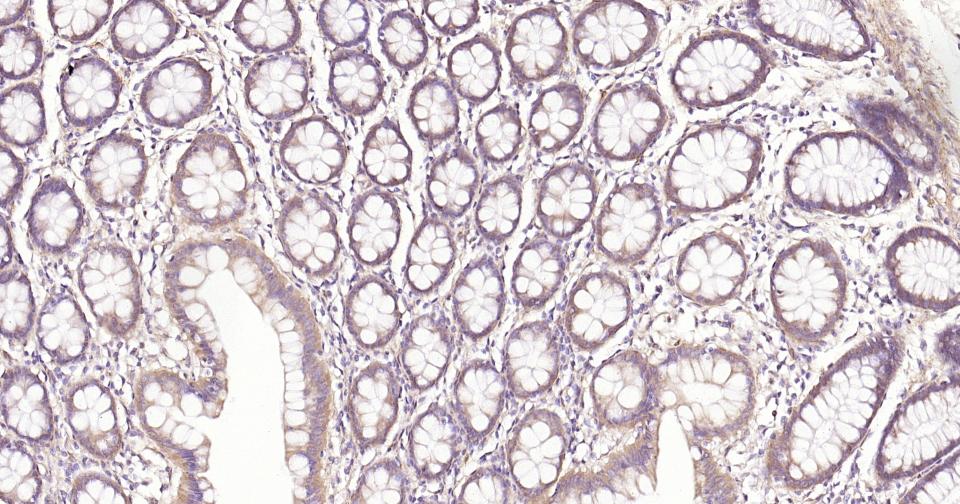

Paraformaldehyde-fixed, paraffin embedded Human Colon; Antigen retrieval by boiling in sodium citrate buffer (pH6.0) for 15 min; Antibody incubation with NFKB p65 Monoclonal Antibody, Unconjugated(bsm-52305R) at 1:200 overnight at 4°C, followed by conjugation to the SP Kit (Rabbit, SP-0023) and DAB (C-0010) staining.

Paraformaldehyde-fixed, paraffin embedded Rat Colon; Antigen retrieval by boiling in sodium citrate buffer (pH6.0) for 15 min; Antibody incubation with NFKB p65 Monoclonal Antibody, Unconjugated(bsm-52305R) at 1:200 overnight at 4°C, followed by conjugation to the SP Kit (Rabbit, SP-0023) and DAB (C-0010) staining.

Paraformaldehyde-fixed, paraffin embedded Mouse Colon; Antigen retrieval by boiling in sodium citrate buffer (pH6.0) for 15 min; Antibody incubation with NFKB p65 Monoclonal Antibody, Unconjugated(bsm-52305R) at 1:200 overnight at 4°C, followed by conjugation to the SP Kit (Rabbit, SP-0023) and DAB (C-0010) staining.